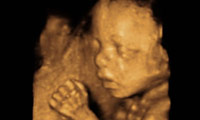

- 内科と婦人科を併設し、乳幼児から老年期まで男女問わず、すこやかな一生と健康を維持するために、地域のかかりつけ医としてお力になれるよう患者さまに安心・安全な誠の医療を提供します。

また総合的な“女性科”として婦人科・妊婦健診・母乳相談などに対応します。 まずはお気軽にご相談ください。

- 産婦人科医として、信州大学附属病院をはじめ県内外の総合病院を勤務してきました。 婦人科疾患全般において診療にあたる所存です。疾患の病状によっては近隣の提携病院と共に診療を行っていきます。また、不妊相談も行なっております。子供が欲しいけどなかなか授からない。それぞれの患者さんの状況に応じて、スクリーニング検査から治療(AIH まで)を行っていきます。